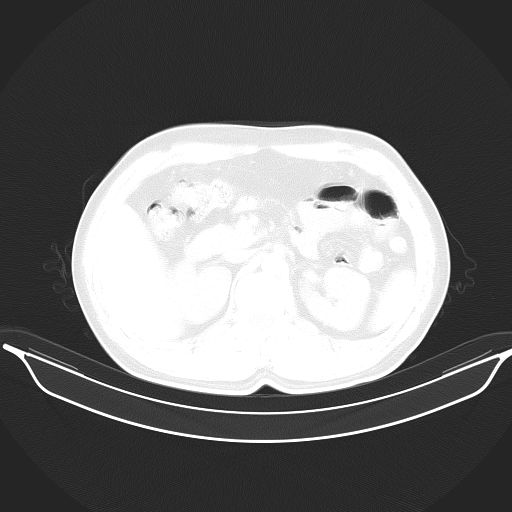

标题: CT25490:男,40岁,体检发现;无其它不适。 [打印本页]

标题: CT25490:男,40岁,体检发现;无其它不适。

2、轻度脂肪肝。